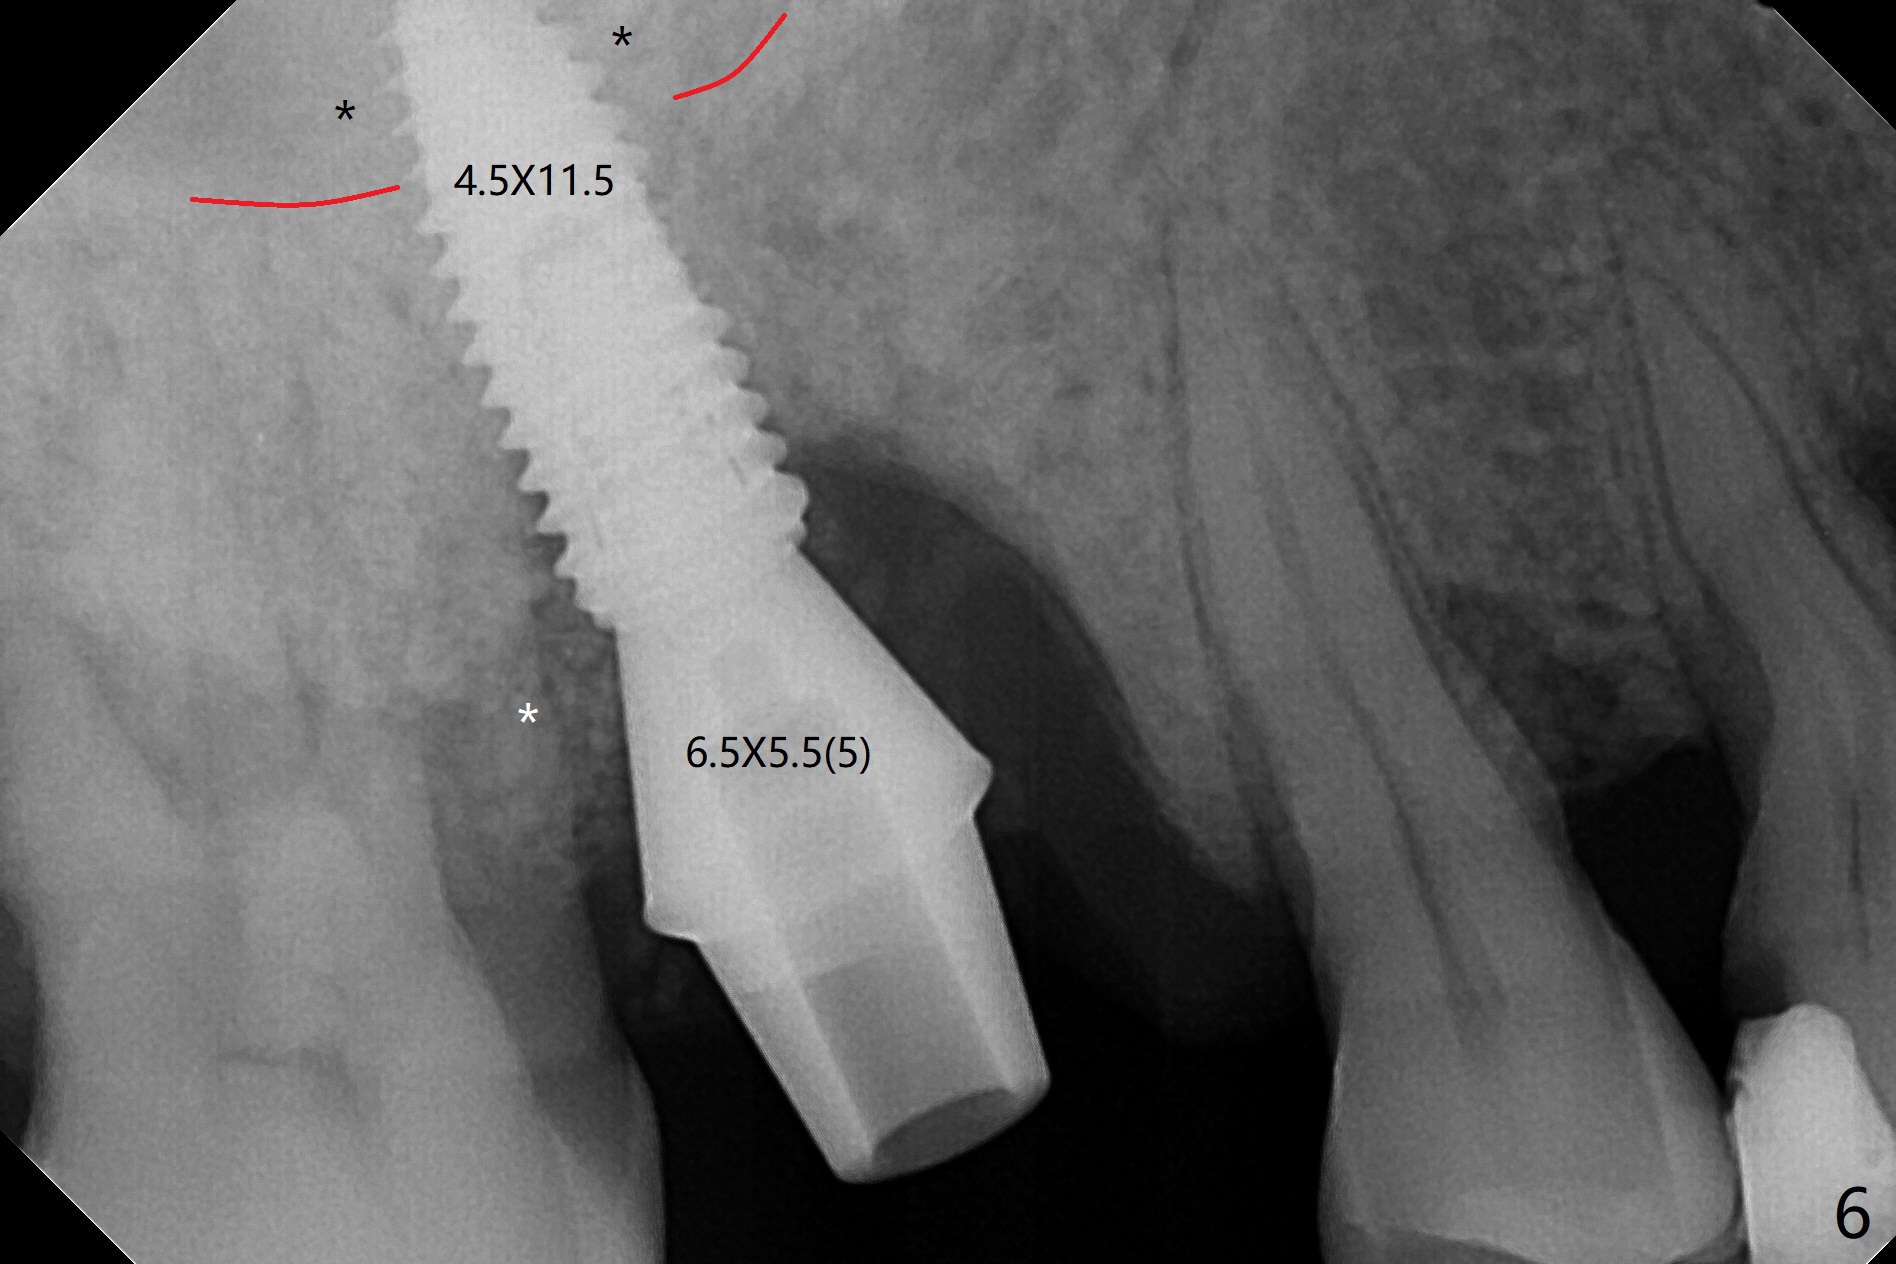

53岁男吸烟,牙周炎,咬合力大,3号牙颊侧(图一),腭侧(图二:P)牙龈退缩,尤其是近中颊侧根(图一:MB),拔牙后,中隔冠方(表面)有好像健康的牙龈(图三:*),近中,远中连接处切开(图三:虚线),将中隔牙龈推向近中颊侧牙槽窝(图四:箭头),修复退缩牙龈,而且暴露下面中隔(S),接着在它上面导板钻洞,避免软组织创伤。利用报废植体试图内提升(图五(红虚线:窦底)),最终正式植体完成提升(图六:黑*),初步在牙槽窝深部放置粘性骨粉(白*)后,放入基台,之后再次在植体,基台周围放置骨粉(图七:*),最后借助临时牙冠(图八,九:T)和外衬里(图八:R)封闭牙槽窝开口,G是近中颊侧迁移的牙龈。植体垂直进入上颌窦可以减少窦膜破裂(图五,六,九),术后没有鼻出血。术后1个月临时牙冠松动,去除牙冠和基台,安置愈合帽(图十)。表面骨粉遗失,但是颊侧移位的中隔牙龈好像帮助软组织预后。